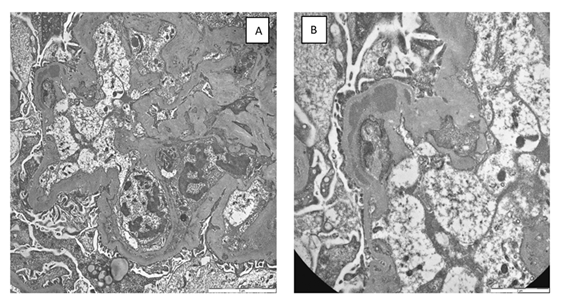

For further diagnostic investigation of nephrotic syndrome, a renal biopsy was performed (june 2023), which showed mesangial hypercellularity with interposition along the wall of the glomerular capillaries. (Figure 1,2). Immunofluorescence revealed finely granular, peripheral, segmental, diffuse positivity for C3 (++) and C1q (+), and negative IgA, IgG, IgM, fibrinogen and kappa and lambda light chains. The patient was diagnosed with C3 glomerulopathy.

Figure 2: a) Transmission electron microscopy: Evidence of diffuse folding of the glomerular basement membrane and interposition of endothelial and mesangial cell cytoplasm. Rare segmentally distributed subendothelial and intramembranous deposits are present. Extensive fusion of the podocyte pedicels. b) At high magnification, a large intramembranous deposit is evident.